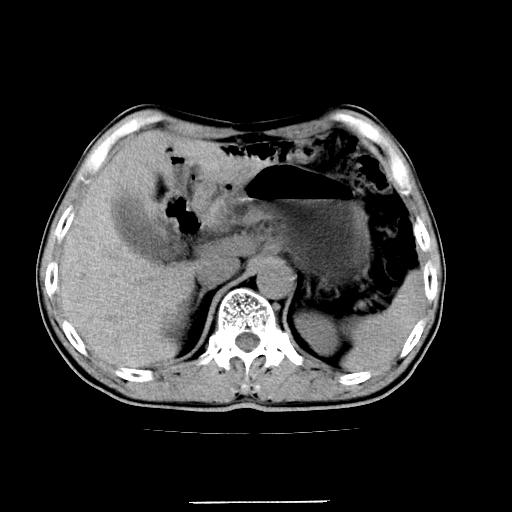

患者男,64岁,胃癌术后三个月,无明显不适。请讨论一下胰头前方小圆形低密度影为淋巴结还是肠管?

增强第6幅图上有气液平相通,是肠管,右肾低密度灶形态不规则似有壁结节,不除外转移.

应该考虑是肠管,理由1、平扫和增强对比,形态和内部的密度有明显改变。2、增强图片可见明显气液平面。

是肠管影,肠壁有强化。

一个形态变化大应该是肠管。

另一个上下观察不成形,强化也不符合淋巴结表现故考虑术后改变。

另外,胰腺体部密度在平扫和增强时均不太均匀,似有数个小的囊状低密度区存在。不知道增强时其他期如何?应该高度警惕为转移性病变。

胰头右侧低密度影卡考虑为肠管;胰头前部低密度影,增强环形强化,结合临床首先考虑转移灶,其次考虑淋巴结结核(中心干酪性坏死)。